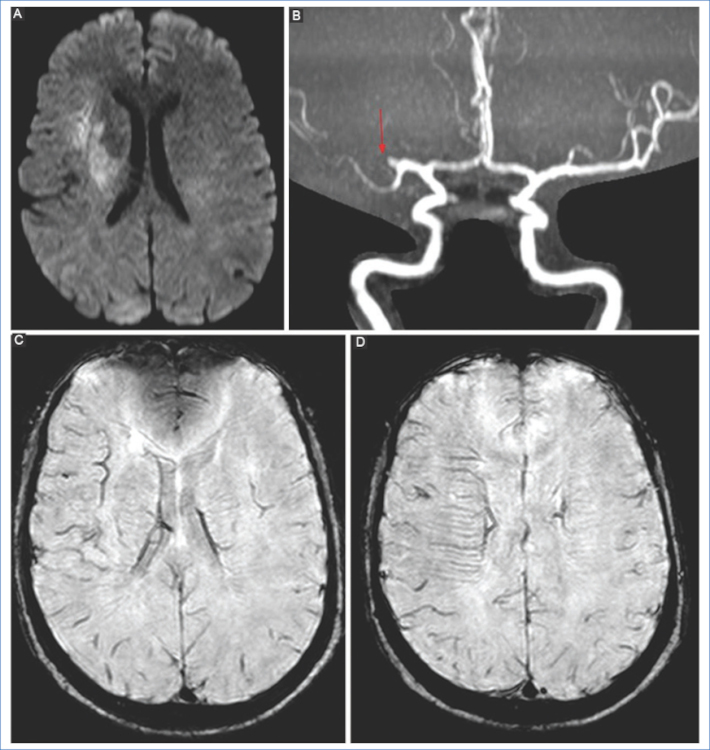

El empleo de secuencias GRE 3D-TOF permite la evaluación de la circulación intracraneal sin la utilización de medios de contraste endovenosos. La utilidad de la angio-RM es determinar la presencia de una oclusión proximal de un vaso de mediano calibre intracraneal para considerar la terapia de revascularización endovascular dentro de las primeras horas. La localización de la oclusión/coágulo predice el éxito de la recanalización2.

Las secuencias angiográficas en la disección de la ACI pueden mostrar oclusión total con preservación del bulbo, o un segmento largo e irregular de estenosis filiforme por estrechez de la luz y engrosamiento parietal debido a hemorragia intramural (signo del collar de perlas) y/o pseudoaneurismas22 (Fig. 9). En la RM de las disecciones extracraneales, las secuencias ponderadas en T1 con saturación grasa son el mejor método para visualización del hematoma mural hiperintenso en las fases subagudas, debido a la metahemoglobina en el lumen falso13.

Las limitaciones de la angio-RM en relación con la angio-TC son el mayor tiempo de exploración, la imposibilidad de evaluar la pared vascular (con secuencias TOF) y que se requieren dos secuencias diferentes para evaluar los vasos intracraneales y los vasos del cuello.